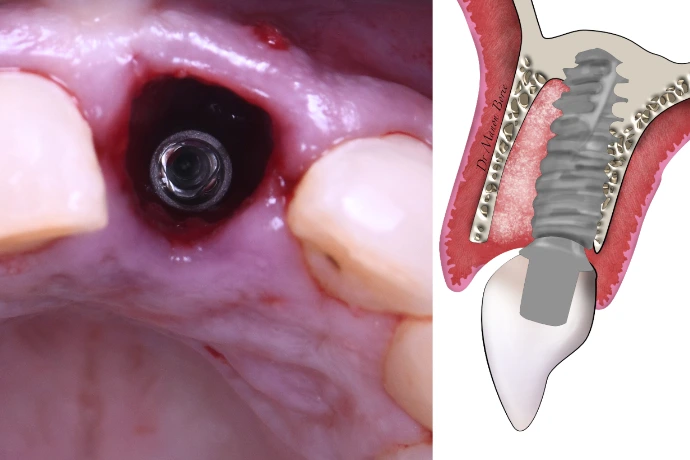

Préservation alvéolaire, régénération osseuse simple et optimisation mucogingivale.

TP : lambeaux, greffes conjonctives et épithélio-conjonctives sur mâchoires animales, ROG péri-implantaire.

Observation directe et participation duo praticien/assistante en chirurgie live.

Possibilité d’intervenir sur vos patients dans un cadre sécurisant.